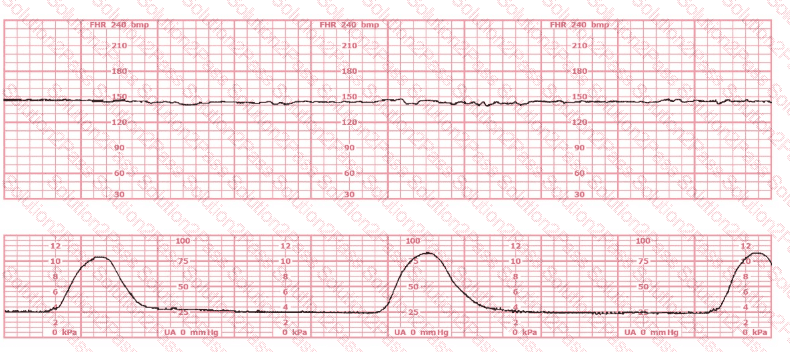

The pattern on the fetal heart rate tracing shown is likely due to

The fetal heart rate tracing shown demonstrates:

The tracing shown is a:

The most probable underlying fetal physiologic cause for this tracing would be:

The fetal heart rate tracing shown is obtained upon the woman's admission to labor and delivery. This tracing is most consistent with what maternal condition?